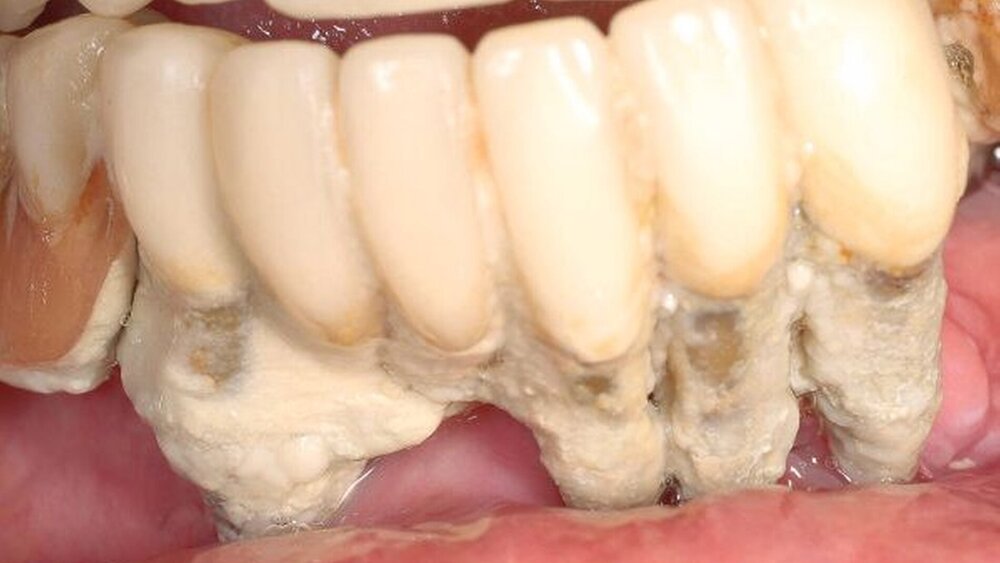

Die 51-Jährige ansonsten sehr gepflegte Patientin hat eine Zahnarztphobie und schon seit Jahren beide Prothesen nicht mehr herausgenommen, da sie wusste, dass die Zähne immer gleich mit den Prothesen herauskamen.

Die Alveolen waren mittlerweile auch schon geschlossen, die natürlichen Zähne standen in Mulden vor dem Alveolarkamm.

Ein Fall, wie man ihn nicht alle Tage sieht! Die Patientin wurde zunächst mit einer Interims-Totalprothese versorgt.